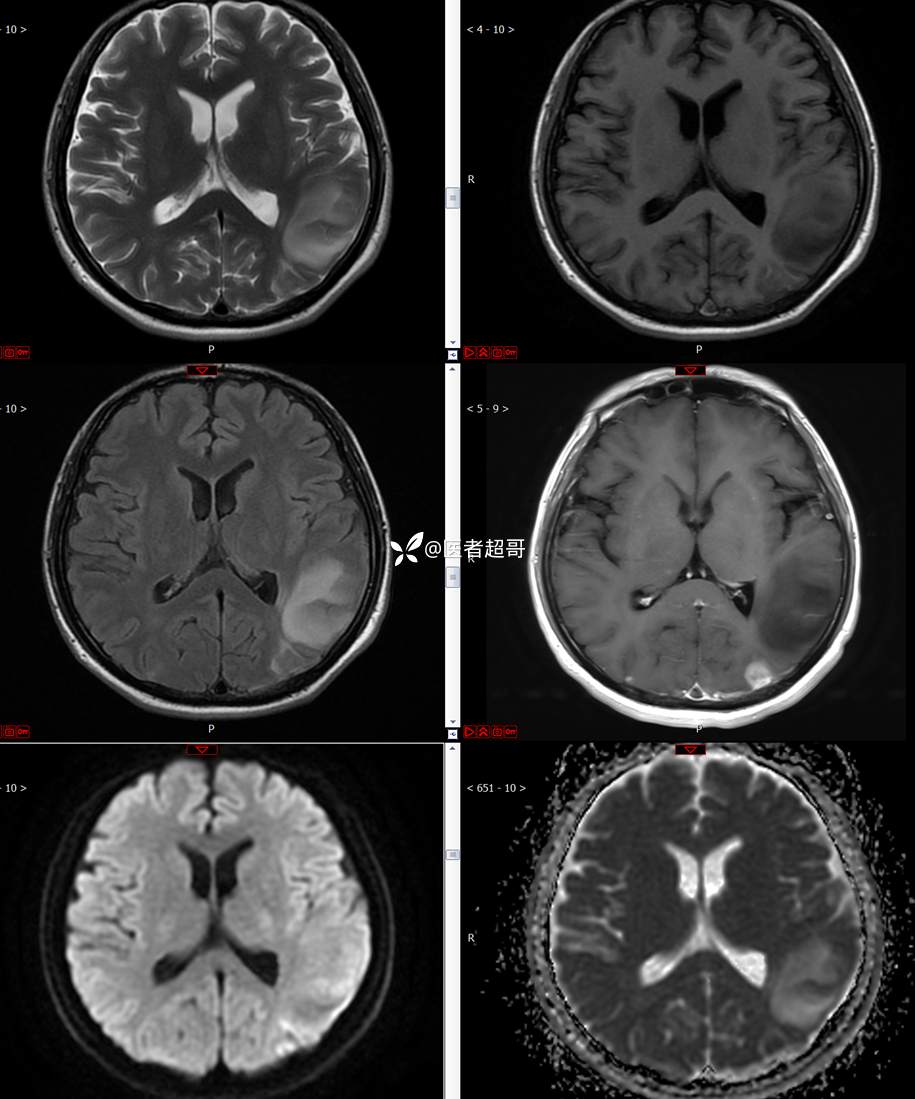

【影诊笔记773】头痛、头晕10天,CT、MRI齐全,请高诊!

主 诉:头痛、头晕10天

现病史:患者10天前无明显诱因感头痛、头晕,伴记忆力减退,无恶心、呕吐,无肢体抽搐及肢体活动不灵等,于我院就诊,行颅脑MR示颅内多发占位,现患者为求进一步治疗于我院就诊,以“颅内占位”收入我科。患者目前神志清,精神可,饮食、睡眠正常,体重无明显变化。

既往史:既往急性肝功能衰竭病史.